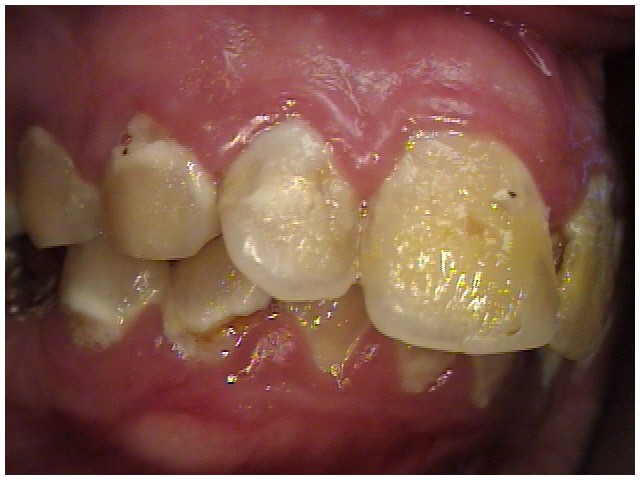

In Figure 7 through Figure 9, the young woman shown had many adverse childhood experiences and was given methamphetamine by an adult when she was 14 years old. She also had her first child at that age, and then had three more children while addicted to meth, though she was only able to retain custody of one of her children. In addition to alcohol, she used meth for 15 years. Her only prosthetic option was extraction of all of her remaining teeth and subsequent placement of complete dentures.

Fig 7 through Fig 9. This young patient’s only prosthetic option was extraction of all remaining teeth and subsequent placement of complete dentures.